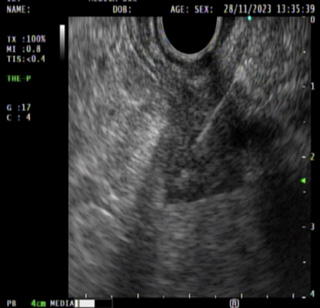

Imagen 3. Biopsia guiada con aguja de tumor de la pared del estómago |